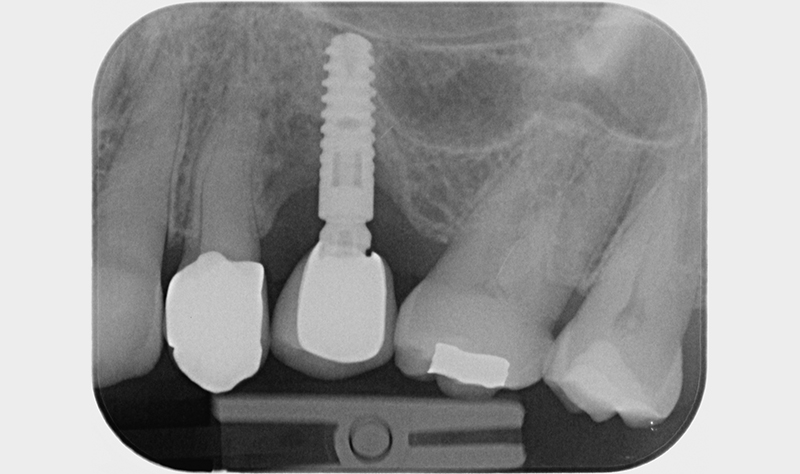

A 6 mesi dal baseline (t4) si esegue rivalutazione. La paziente viene sottoposta a esame radiografico e documentazione fotografica (Figs. 8-9). All’esame visivo i tessuti molli perimplantari si presentano in buono stato, in termini di colore e consistenza.

All’esame radiografico si apprezza una remineralizzazione dell’osso. Viene valutata dal chirurgo l’eventualità di riposizionamento di tessuto cheratinizzato a gestione della recessione gengivale, ma si decide di aspettare. Il buon mantenimento domiciliare della paziente ha reso sufficiente un air polishing sopragengivale con polvere di glicina, al fine di disgregare eventuale biofilm patogeno, sostenitore di eventuale recidiva. Si esegue anche in questa occasione rinforzo motivazionale.

rivalutazione radiografica dei 6 mesi

Fig. 9 - Rivalutazione radiografica dei sei mesi che mostra aumentata mineralità della componente ossea con neotrabecolatura delle aree del difetto.